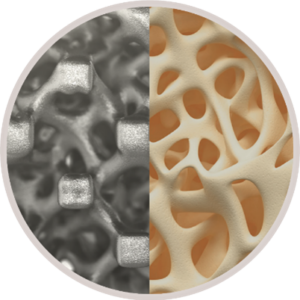

FLX devices participate in the fusion process with a combination of macro, micro and nano structural characteristics that influence cellular events related to the production of new bone. Additionally, the texturized surface and proprietary FUSE-THRU™ osteoconductive trabecular scaffold built into these FLX devices are designed to improve cellular attachment and proliferation, to provide guided bone growth. The FUSE-THRU scaffold mimics the structure of trabecular bone, with a porosity and interconnected pores in size ranges that have been shown to be optimal for rapid and sustained bone growth.

“3D printing provides the opportunity to rethink the way implants can deliver better quality of life for patients in need of spinal fusion,” said Jamie Manos, Centinel Spine Fusion Product Director. “Creating a fully titanium implant with a complex lattice scaffold designed to enable bony on-growth, in-growth and thru-growth, with good imaging properties and a subsidence profile similar to PEEK is something that simply isn’t possible with traditional manufacturing methods, and is a game changer in the interbody space.”